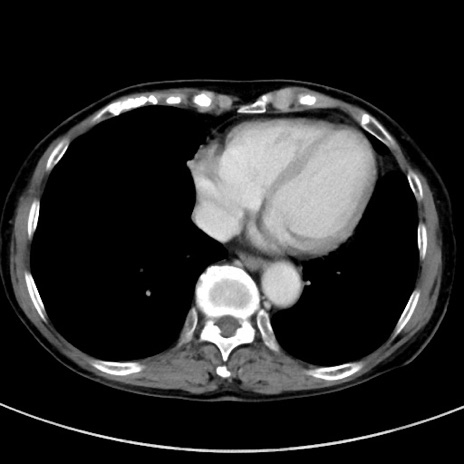

症例23(横断像)

【症例】70歳代女性

【主訴】下腹部痛・嘔吐

【現病歴】2日前より腹痛あり。昨日嘔吐あり。症状改善しないため来院。

【既往歴】胃GISTに対して胃部分切除後。

【身体所見】BT 37.1℃、BP 128/77mmHg、腹部:平坦・軟、下腹部に圧痛あり。

【データ】WBC 10200、CRP 0.31